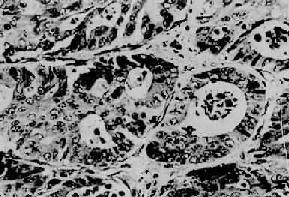

图10-3 慢性萎缩性胃炎

幽门腺大部分萎缩消失,胃小凹延长,有潴留性小囊形成,腺上皮中杂有不少杯状细胞(肠上皮化生),固有膜内有不少慢性炎性细胞浸润(Ⅱ74-4950)